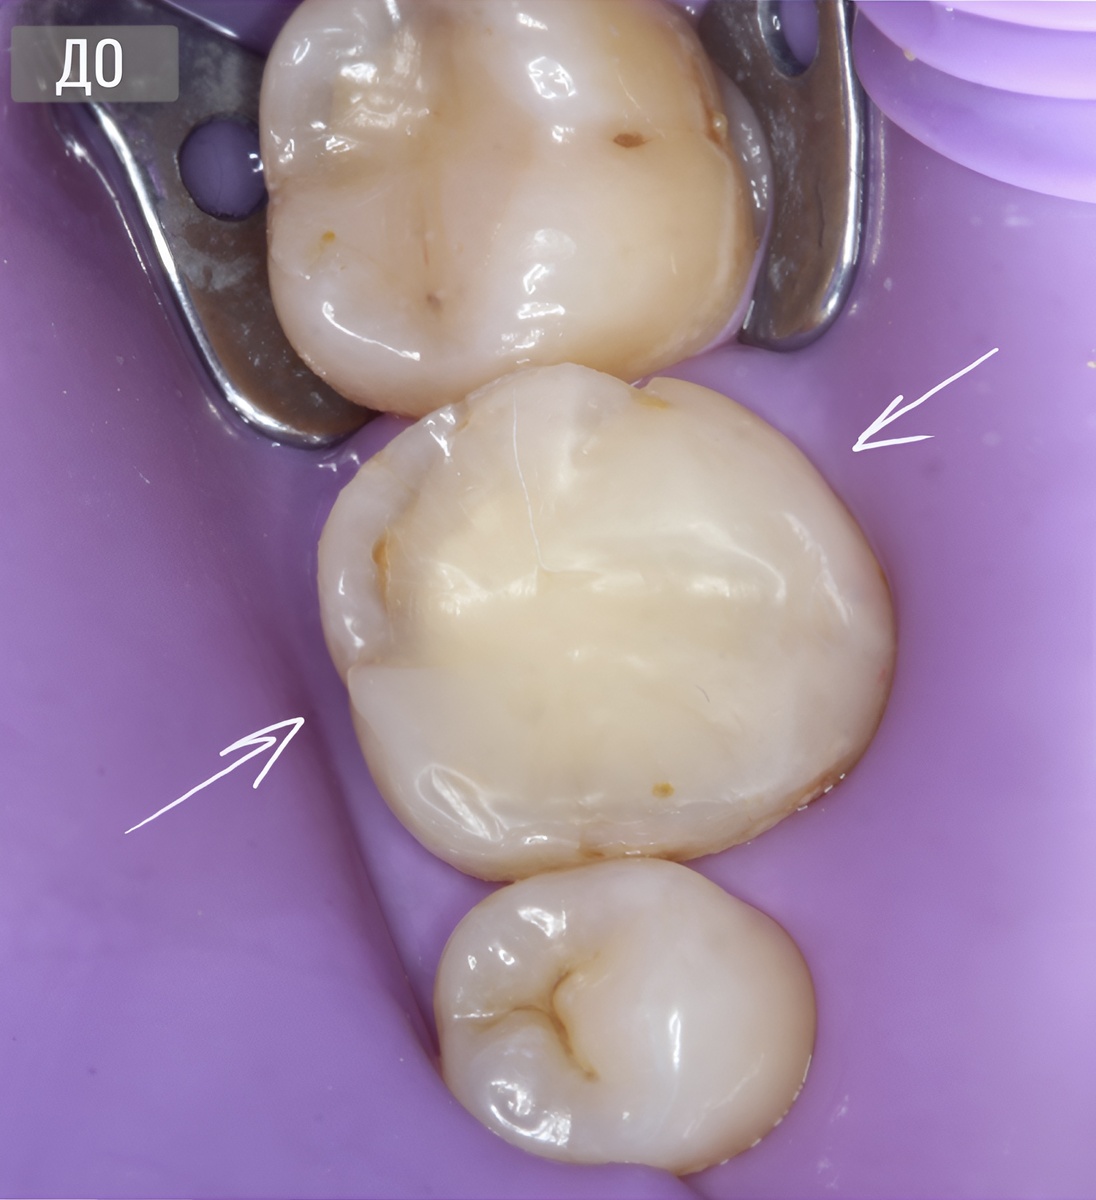

Зуб на момент обращения

Пациент просто отметил дискомфорт в области зуба.